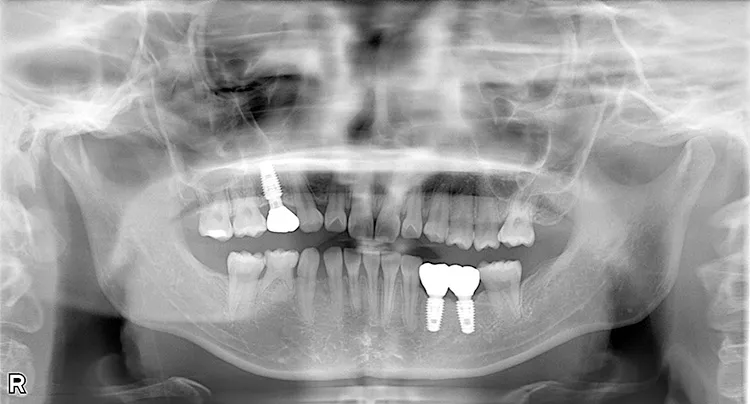

左下の大臼歯の欠損を長期間放置したために上の歯が下がってきてしまい、他の歯医者で被せを入れることができないと断られうちに来られました。下がってきてしまった上の奥歯を部分矯正で上に引っ張り上げ、下に被せ物を入れるスペースを作り、インプラントを入れて噛み合わせを回復しました。部分矯正開始から1年半で治療完了しました。

治療内容

左下67 欠損に対してインプラント治療を行った症例

部分床義歯を使用していたが、どうしても慣れない上にしっかり噛むことができないためインプラント治療を希望